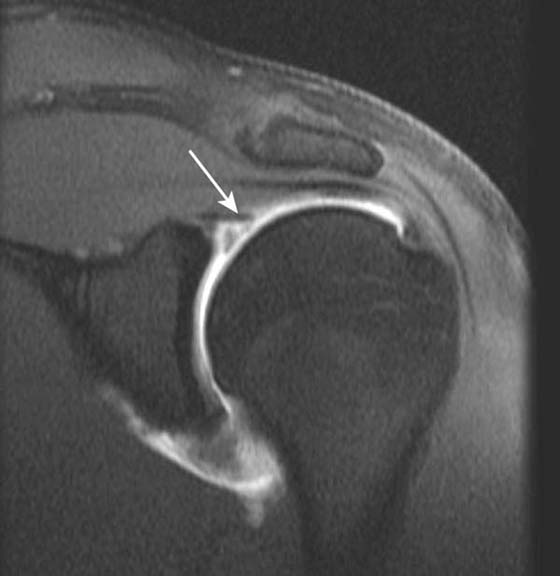

US is also a valuable tool in the assessment of impingement18 and is useful for the evaluation of rotator cuff pathology (Fig. 14-8) although it cannot give a global assessment including labral, capsular, cartilage, and marrow pathology. US is useful in the setting of rotator cuff repair and is particularly useful in shoulder arthroplasty where susceptibility artifact from the metallic prosthesis on MRI would limit interpretation of the adjacent cuff.19 In addition, calcific tendinosis of the rotator cuff is well demonstrated on US20 and is often amenable to SASD bursal injection of steroid and anesthetic or needling in refractory cases.

images

Figure 14-8 Partial-thickness rotator cuff tear. Ultrasound along the long axis of the distal supraspinatus tendon adjacent to its insertion on the greater tuberosity demonstrates a focal partial undersurface tear (arrow) as indicated by a hypoechoic (dark) defect.

Direct MR arthrography is most useful in detecting suggested injury to the medial and lateral stabilizing ligaments. The medial (ulnar) collateral ligament, for example, is frequently injured in baseball pitchers and can be assessed accurately with MR arthrography34-36 (Fig. 14-13). US is also useful in assessing the elbow ligaments but has an advantage over MRI with its ability to assess ligamentous laxity in real time with dynamic imaging37,38 (Fig. 14-14). For example, during valgus stress for assessment of the medial collateral ligament, a difference in 2 mm between sides is diagnostic of abnormal ligamentous laxity.

Figure 14-14 Ulnar collateral ligament (UCL) instability. A, Ultrasound at rest. Medial elbow joint demonstrates minimal gapping between the trochlea of humerus and ulna measured by crosshairs. B, When manual valgus stress is applied this gap increases significantly (difference of 3.9 mm) consistent with UCL instability. The difference between rest and stress measurement should be less than 2 mm. Multiple measurements (e.g., 3) should be taken and the average calculated. It is also useful to compare with the asymptomatic elbow.